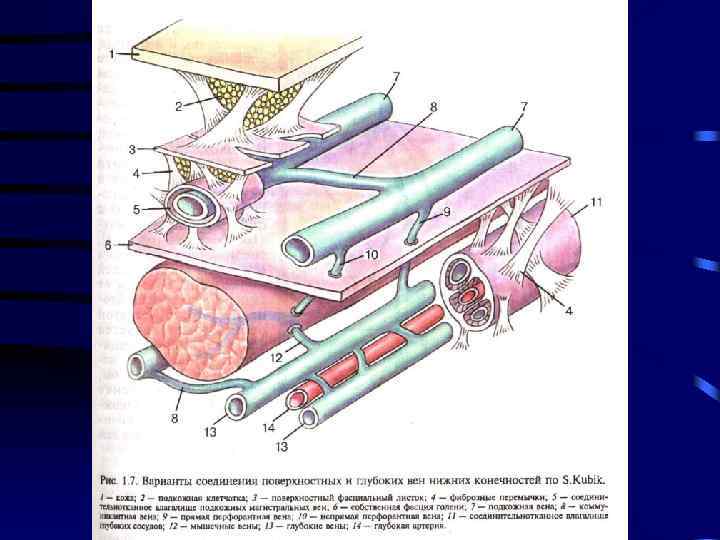

Острый тромбофлебит – острое воспаление венозной стенки с образованием тромба в просвете сосуда с нарушением оттока крови по вене. • По месту локализации различают: • • Тромбофлебит подкожных вен Тромбофлебит глубоких вен Тромбофлебит подвздошных вен Тромбофлебит подключичной вены – синдром Педжета-Шреттера

• Для возникновения тромбоза необходимо 3 фактора: 1. 2. 3. Повреждение сосудистой стенки при травме, воспалении, аллергии Изменение физико-химических свойств крови, обезвоживание, нарушение нервной регуляции жидкого состояния крови (свертывающей и противосвертывающей систем), воздействие токсинов Замедление тока крови